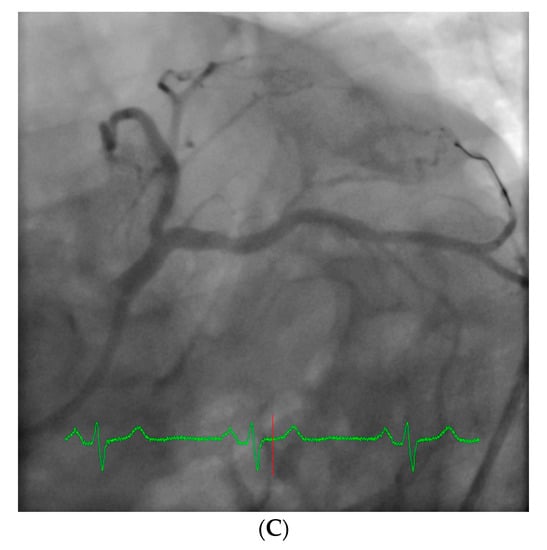

However, an ideal robotic intervention is one where the operator obtains access and performs initial guide placement manually, and is then able to complete the entire intervention from the cockpit without having to re-scrub, even briefly, to perform some portion manually. An example of an excellent case for robotic PCI is a two vessel PCI of the left anterior descending and circumflex arteries, where one guide shape and a single guidewire is used for both vessels, and where significant radiation exposure or a prolonged time in lead are both avoided. Figure 2 shows an example of an ideal robotic PCI case.

Figure 2.

Example of an ideal case for robotic PCI. These images are from a 72 year-old with unstable angina referred to our hospital for intervention. Diagnostic catheterization showed moderate disease in the LAD (A) but with fractional flow reserve of 0.65 and severe disease of the LCX (B) with chronic occlusion of the RCA. The LAD and LCX were both treated successfully robotically with post-stent images shown in (C).